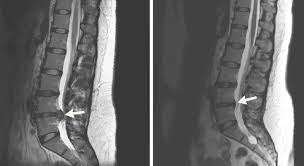

Wird ein Bandscheibenvorfall zwischen L5S1 früh diagnostiziert so ist eine rein konservative Therapie in den meisten Fällen vollkommen ausreichend. Die meisten Menschen mit einem Bandscheibenvorfall im Lendenwirbelbereich werden konservativ behandelt das heißt ohne Operation. Ich möchte mal im kurzen meinen Leidensgeschichte wiedergeben.

Hallo zusammen auch mich hat es leider mit 28 Jahren voll erwischt Im August bekam ich die Diagnose Bandscheibenvorfall L5S1. Wir empfehlen in diesen Fällen die Durchführung einer physikalischen Therapie in Verbindung mit Krankengymnastik sowie die vorübergehende Einnahme von Schmerz- bzw. Die PRT also die periradikuläre Therapie bietet eine effektive Methode der Behandlung von Schmerzen bei einem Bandscheibenvorfall in der LWS.

Eventuell kann auch eine gezielte Spritze an die Nervenwurzel zur lokalen Abschwellung sinnvoll sein. Wichtig ist dass eine Bettruhe und körperliche Schonung verhindert werden. Vor allem bei einem frischen oder wenig ausgeprägten Bandscheibenvorfall zwischen L5S1 können konservative Behandlungsmethoden beispielsweise spezielle Übungen und Physiotherapie hilfreich sein.